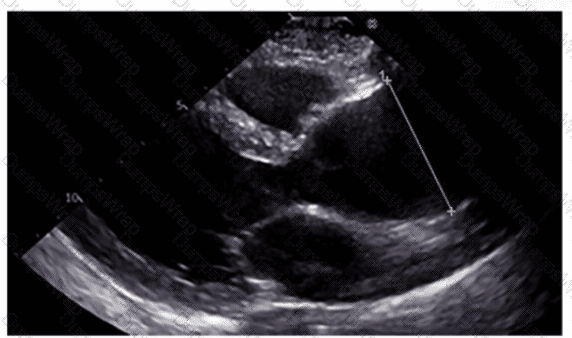

Which anatomic structure is represented by the arrow on this image?

DExplanation:

The echocardiographic image is a four-chamber view focusing on the mitral valve apparatus. The arrow points to the anterior leaflet of the mitral valve, which is typically more prominent, triangular in shape, and located adjacent to the aortic valve in the left ventricular outflow tract region.

The posterior leaflet of the mitral valve is generally smaller, has multiple scallops, and is located posteriorly relative to the anterior leaflet. The septal leaflet is part of the tricuspid valve on the right side of the heart. The "left leaflet" is a non-specific term and not an anatomical descriptor.

This differentiation between anterior and posterior leaflets is important for understanding mitral valve pathology and for interventions such as mitral valve repair. These features are clearly explained in echocardiography texts and ASE valve imaging guidelines【12:ASE Valve Imaging Guidelines†p.180-185】【16:Textbook of Clinical Echocardiography, 6e†p.200-205】.